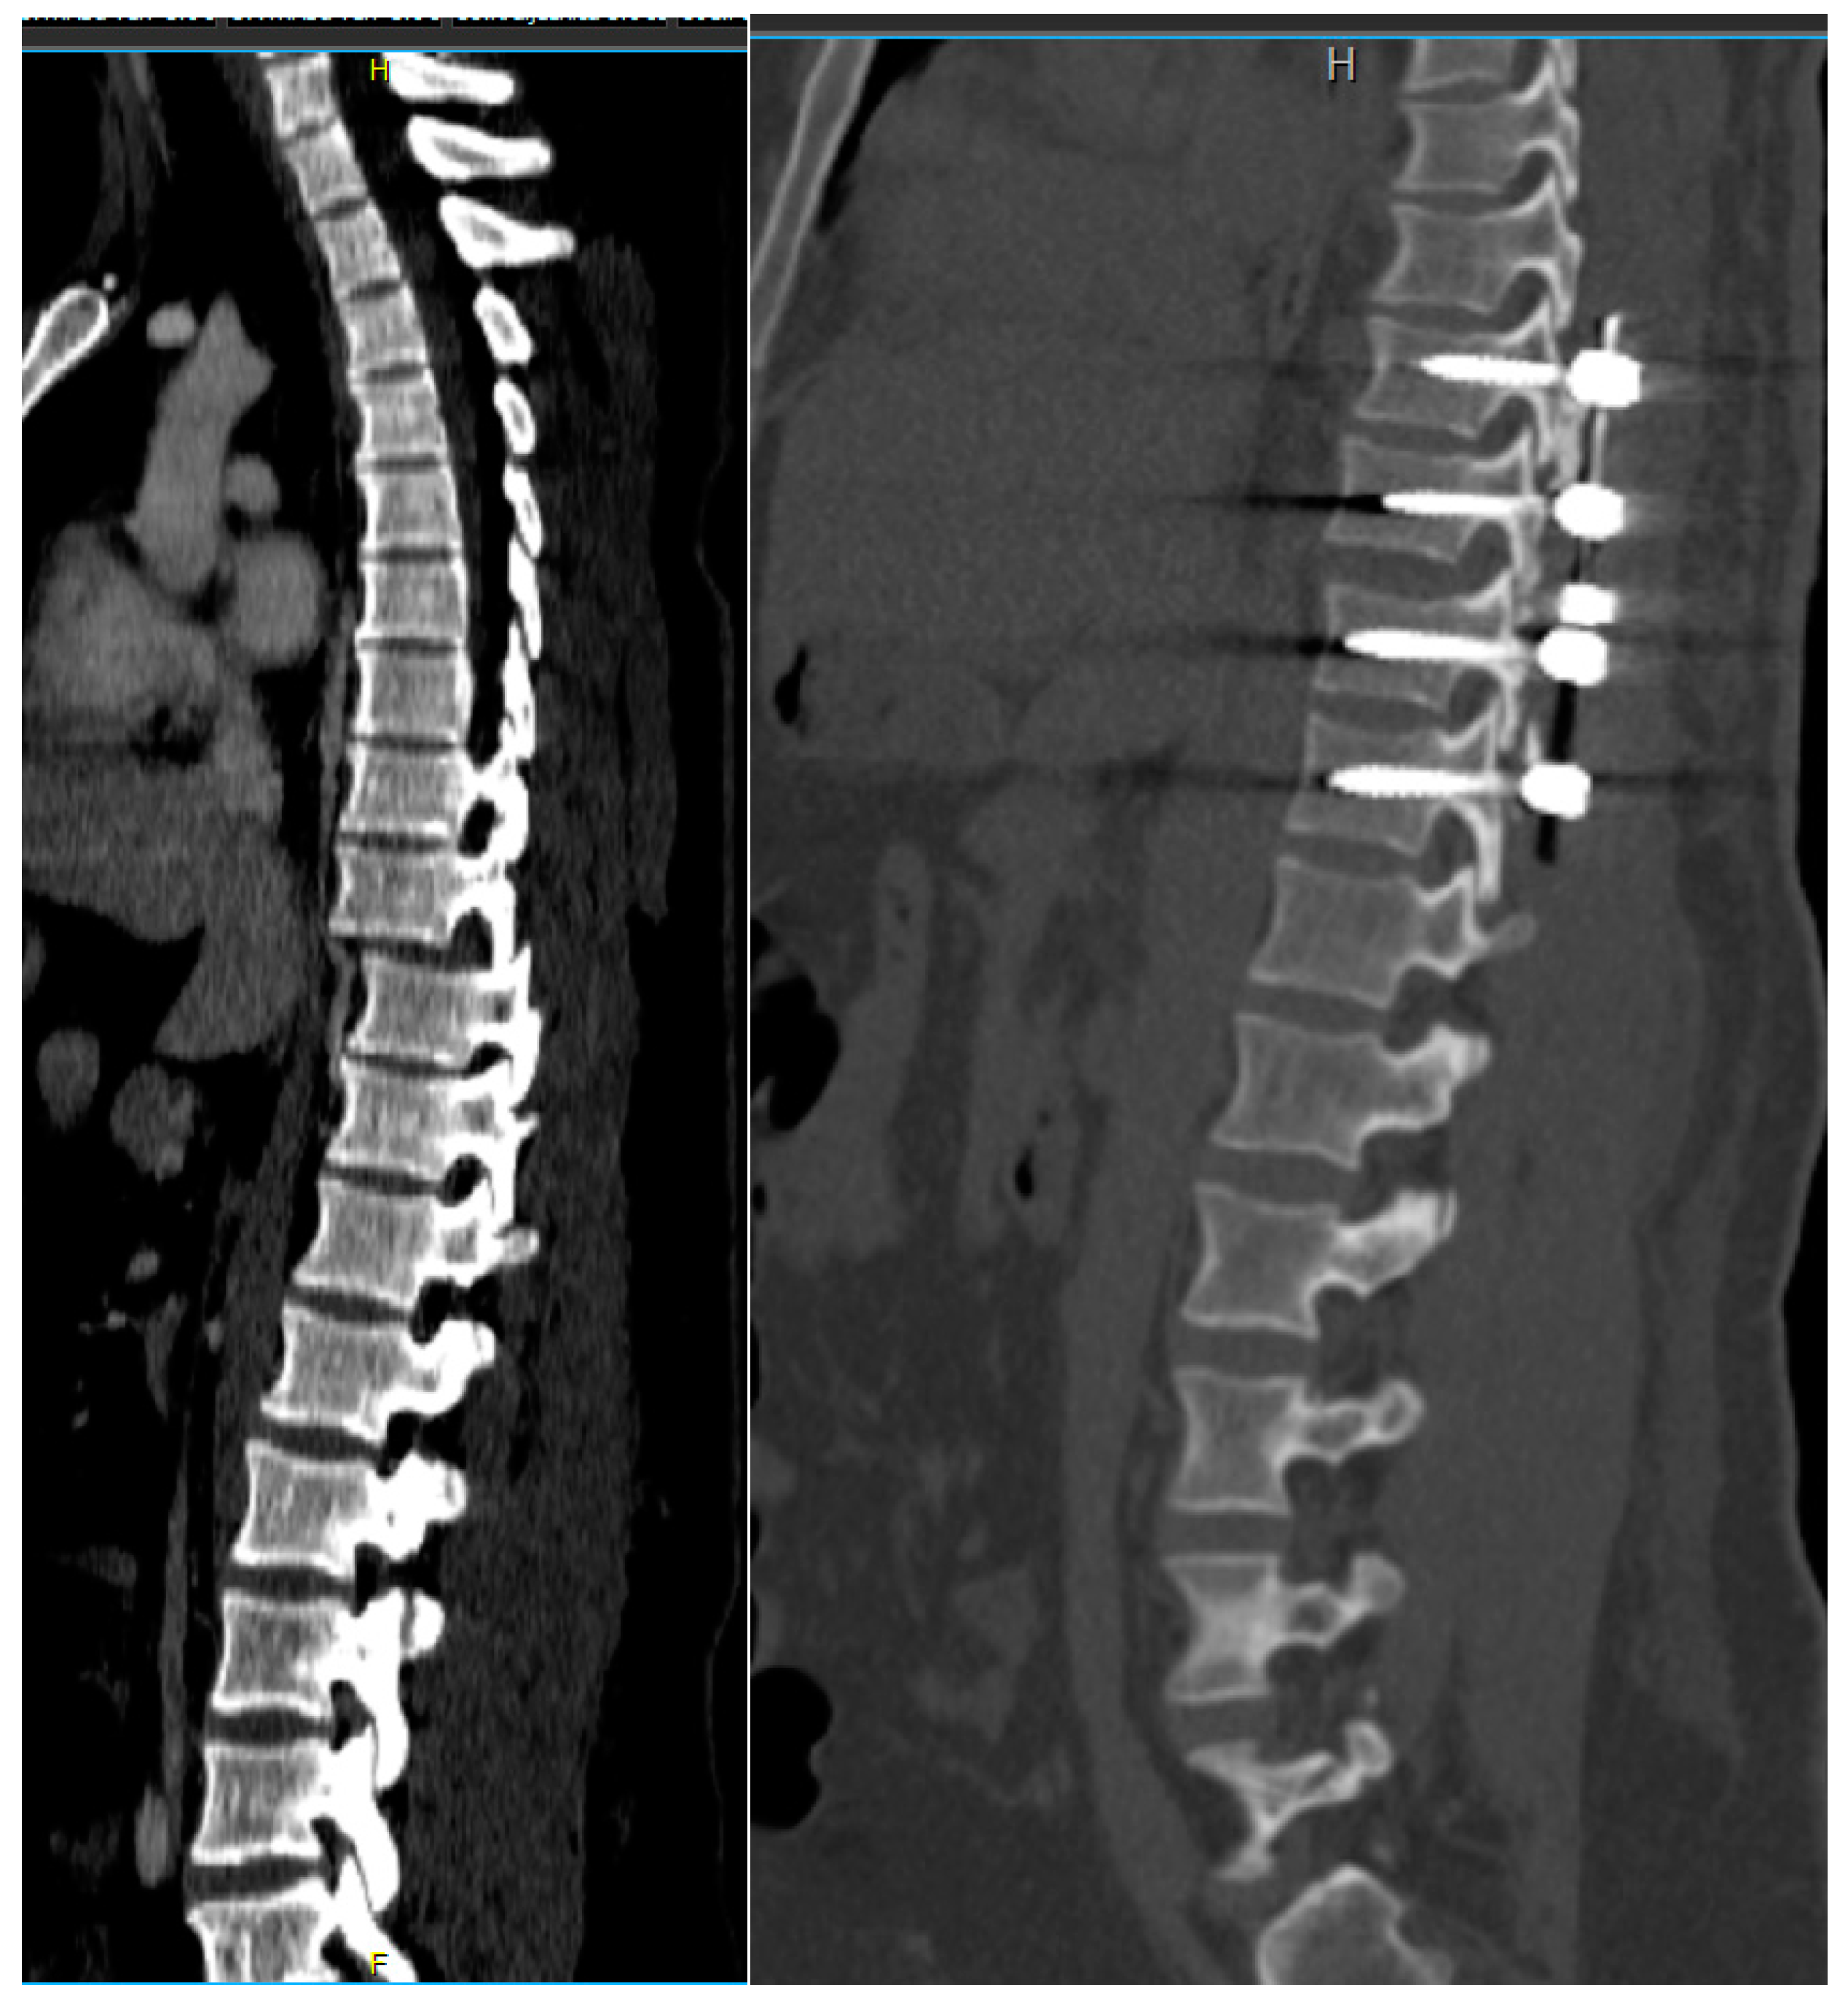

Figure 6.

Intraoperative fluoroscopic images after successful reduction, decompression, and posterolateral fusion of Th10-L1. Yellow lines represent the vertebral body height and the translation that is restored with the surgical fixation.

Figure 7.

Computerized tomography scan of thoracic fracture–dislocation (Th9/Th10) successfully and safely reduced using the described technique.